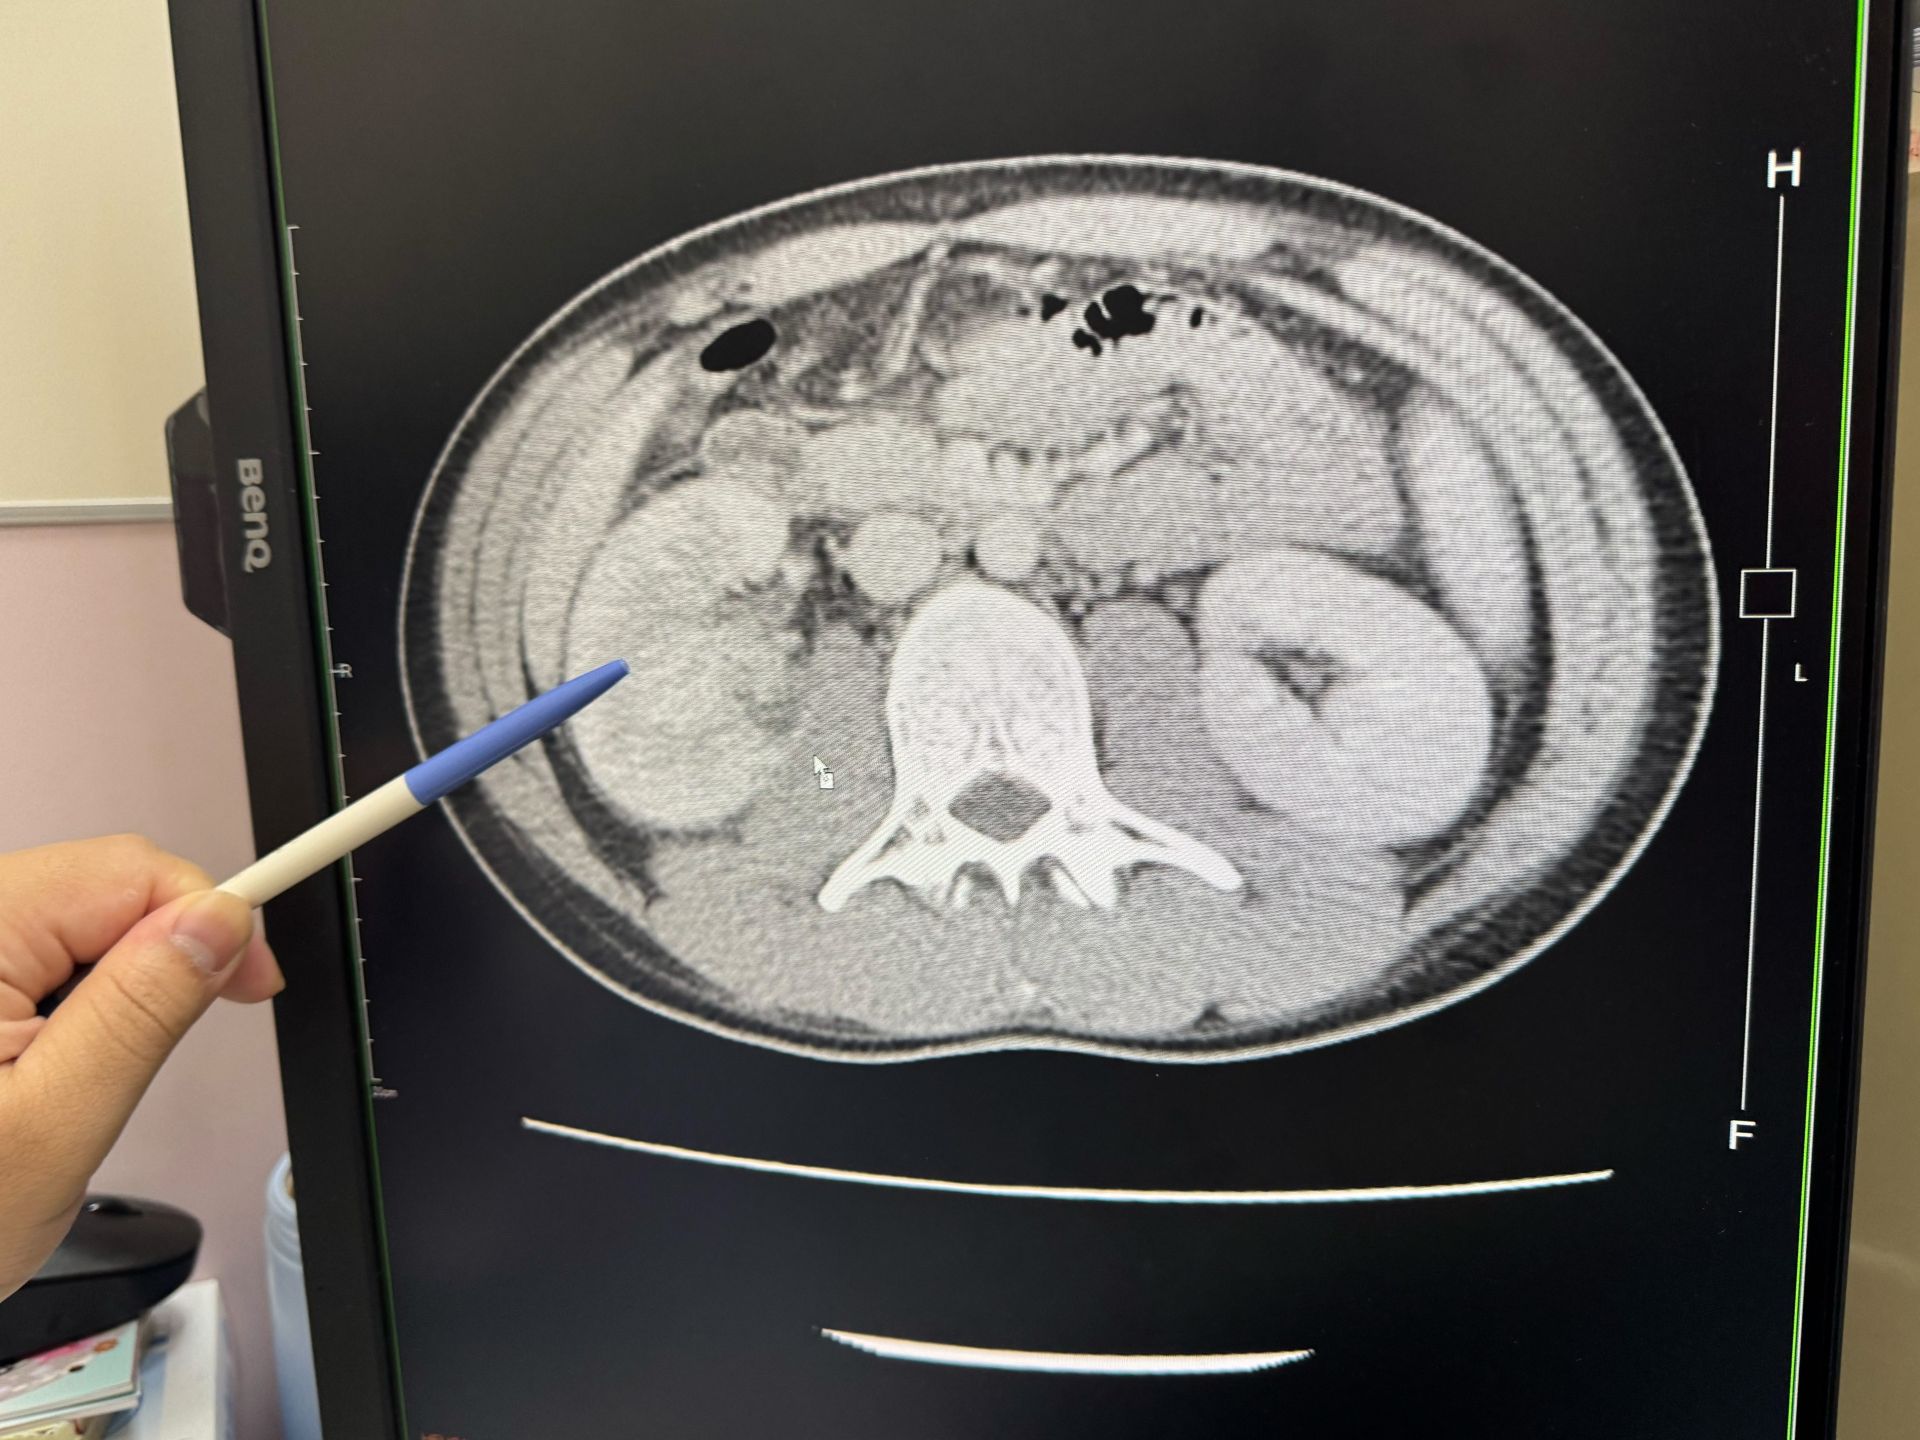

23歲男子罹患急性腎盂腎炎,一邊腎臟腫大一倍大

大甲李綜合醫院泌尿科主治醫師黃品叡表示,患者因反覆發燒找不出原因、出現畏寒而自行到急診就醫,檢查後發現,右邊腎臟有兩個0.1公分小的結石,而且右腎腫大是左腎的一倍大,發炎指數飆高到27 mg/dL,是一般正常0.3 mg/dL的90倍,趕緊安排住院治療。